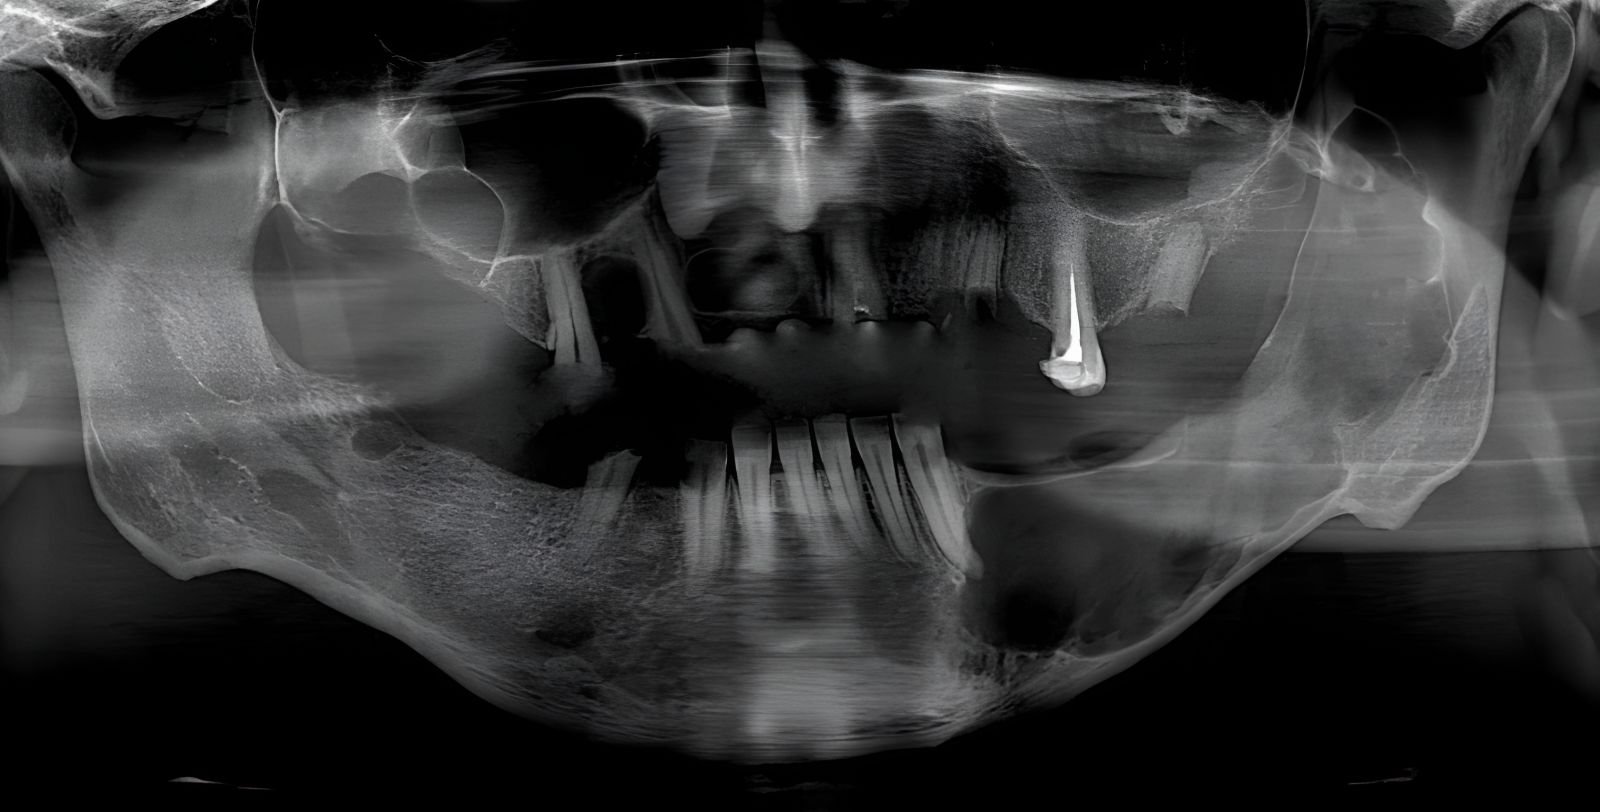

يصارع الناشط الفلسطيني السوري “أيمن دواه”، من أبناء مخيّم اليرموك المهجر إلى منطقة أسنيورت بمدينة إسطنبول مرضاً خطيراً: سرطان الأنمو بلاسما في الفكين – ورم خبيث ينهش عظامه ويحول وجهه إلى ساحة معركة يومية مليئة بالألم الشديد والتنفس الصعب.

عاش أيمن التهجير والحرمان، واليوم يواجه مصيرًا أقسى بدون عائلة تدعمه أو علاج يخفف عذابه.، هو اليوم بلا “ربورت طبي” رسمي يفتح أبواب الجمعيات الطبية والخيرية أمامه للدعم والعلاج المجاني.

قصة أيمن تدمي القلب، ف كل لحظة تمر عليه يشعر بها بألم لا يطاق، وكل يوم يعيشه في تركيا بمشقة، المستشفيات التركية – الأفضل لعلاج هذا الورم النادر الذي يتطلب جراحة دقيقة وإعادة بناء الفك – تغلق أبوابه أمامه بدون إقامة إنسانية.